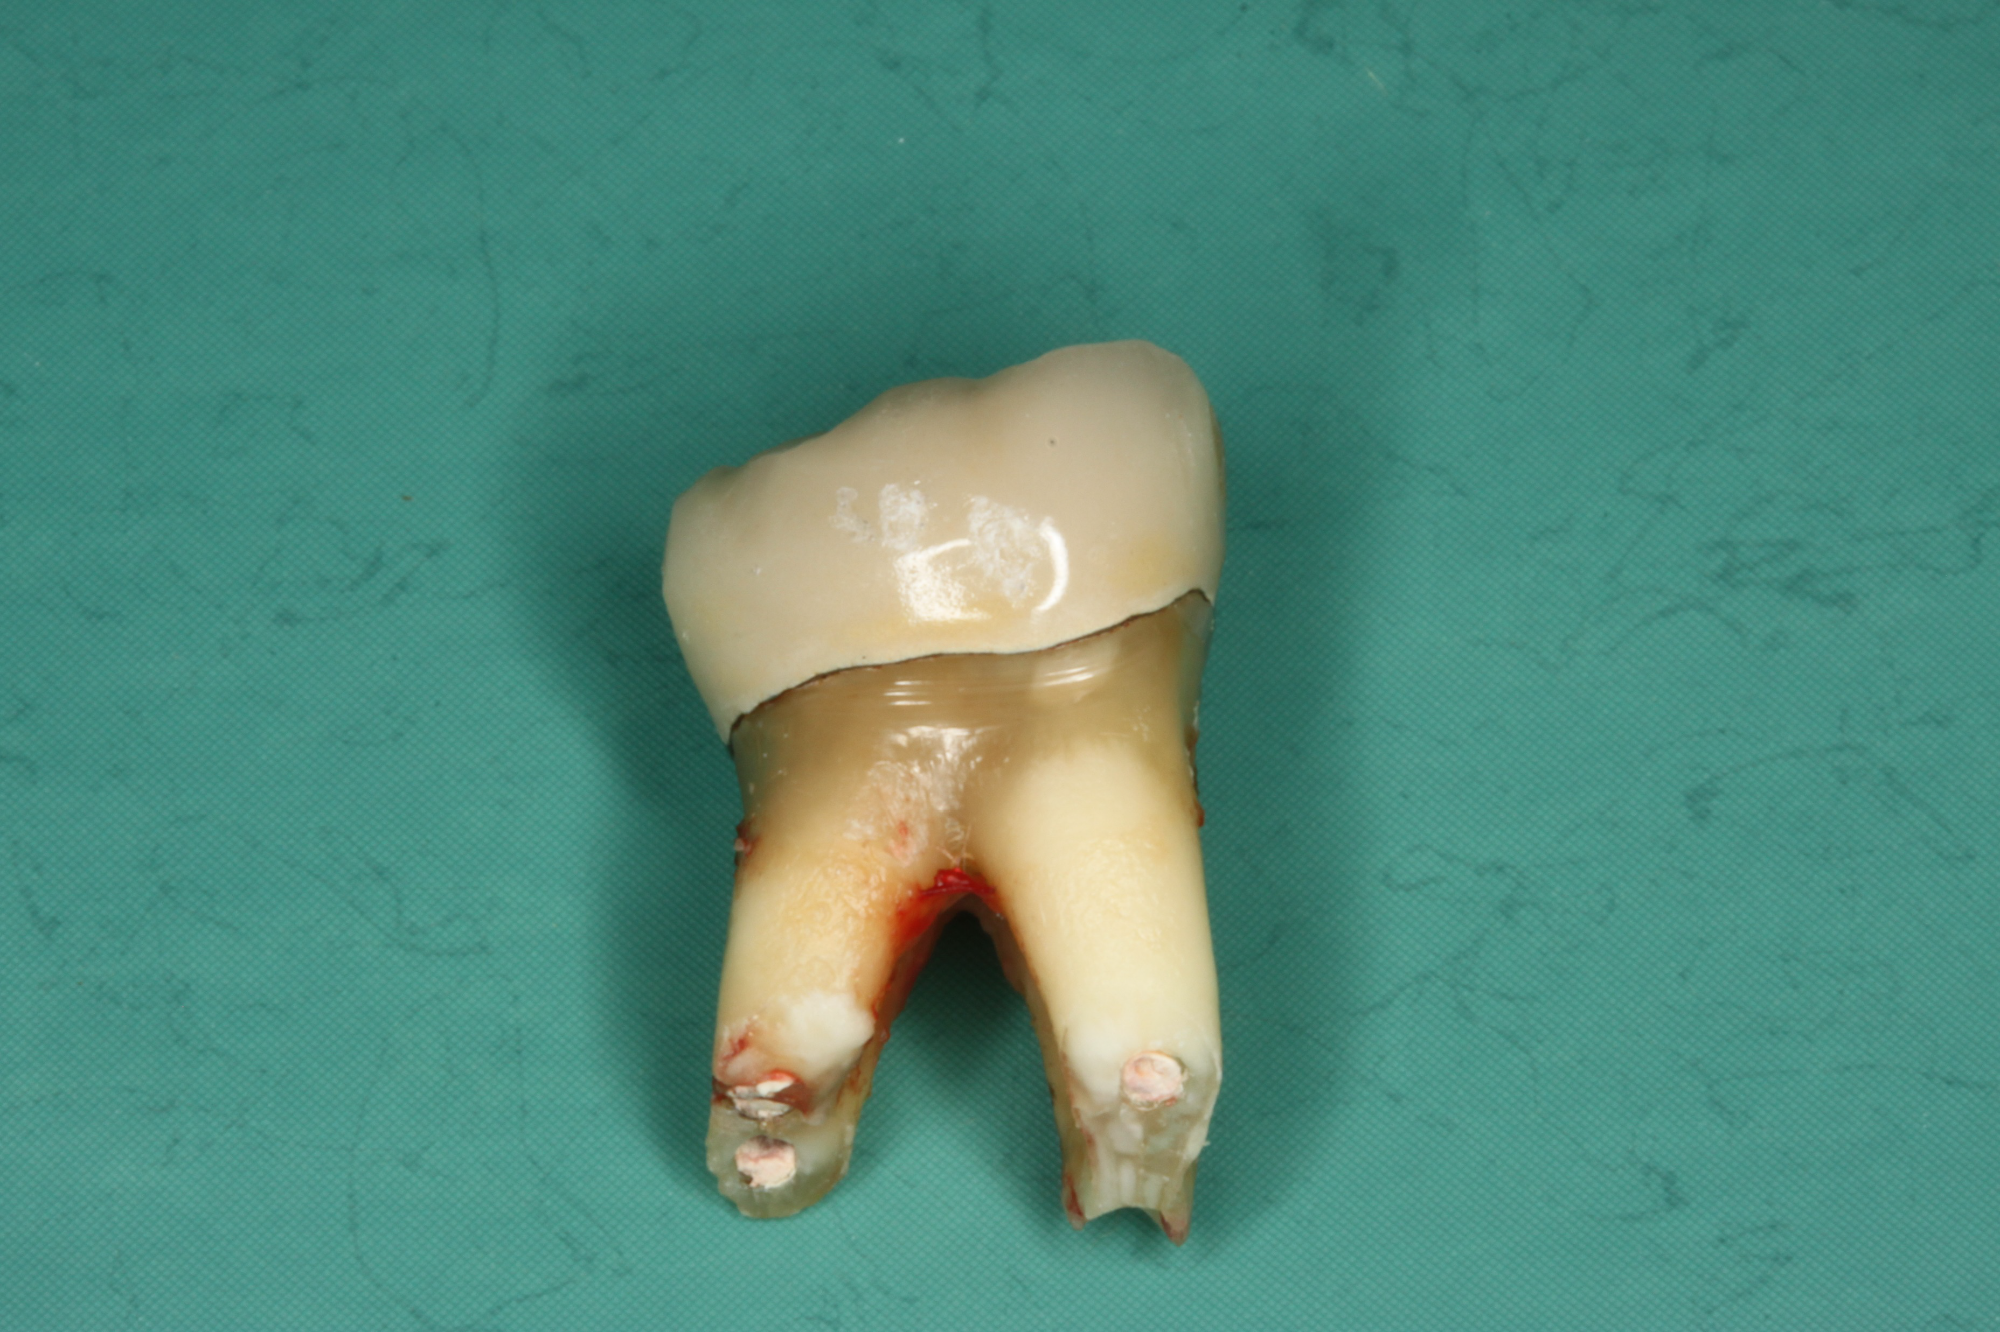

Wurzelkanalbehandelte Zähne sind tote Zähne! Auch die beste Mikro-Endodontie wird kaum eine komplett bakteriendicht abgeschlossene Wurzel realisieren können. Akzessorische Seitenkanäle und die Endo-Paro Verbindung über die Dentintubuli bleiben bestehen.

Die Entfernung wurzelkanalbehandelter Zähne in unserer Praxis

Der Austausch wurzelbehandelter und toter Zähne erfolgt so schonend wie möglich. An die Stelle des toten bzw. wurzelbehandelten Zahnes wird direkt in derselben Behandlung ein Keramikimplantat gesetzt, wenn genug gesunder Knochen vorhanden ist.